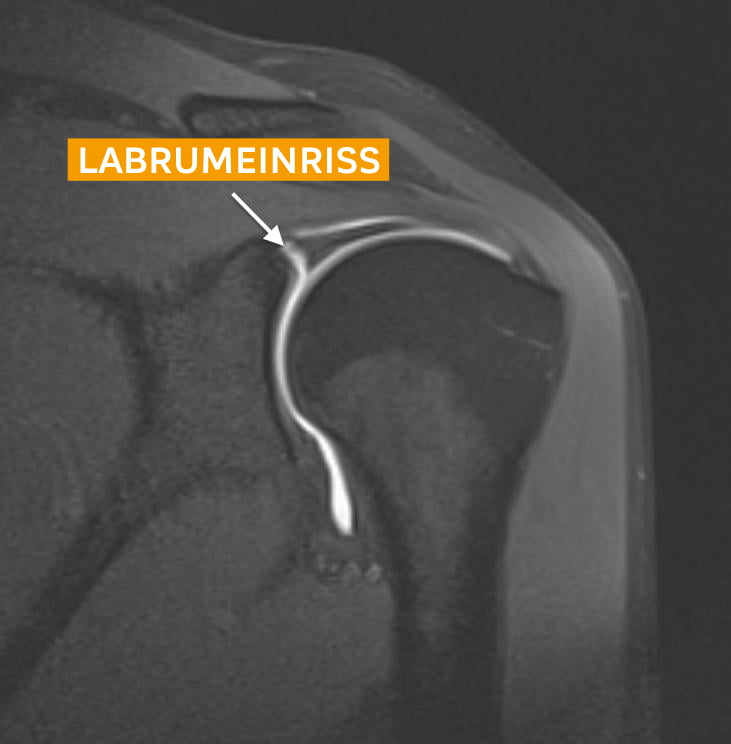

Labrumschaden Beschwerden & Behandlung Die körperliche Untersuchung kann Hinweise auf einen Labrum-Riss liefern, der jedoch im Allgemeinen im MRT bestätigt wird. Etwa 90 % der Patienten erzielen eine vollständige Wiederherstellung. Die Behandlung erfolgt häufig mit rezeptfreien Medikamenten, Kortisoninjektionen und.

Source: bombitupqeg.pages.dev Schulterluxation und Schulterinstabilität Schulthess Klinik , Die körperliche Untersuchung kann Hinweise auf einen Labrum-Riss liefern, der jedoch im Allgemeinen im MRT bestätigt wird. Die Behandlung erfolgt häufig mit rezeptfreien Medikamenten, Kortisoninjektionen und.

The Pathophysiology Behind Braxton Miller’s Torn Labrum Eleven Warriors . Spätestens nach einer Operation ist aber Physiotherapie zur Rehabilitation angesagt. Die körperliche Untersuchung kann Hinweise auf einen Labrum-Riss liefern, der jedoch im Allgemeinen im MRT bestätigt wird.